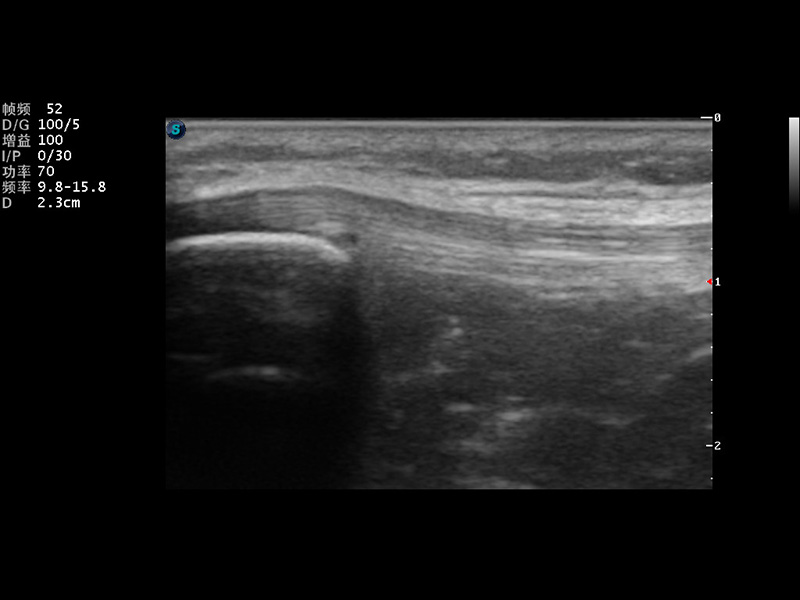

S9便携式彩色多普勒超声诊断仪是环球UG官网研发的高端便携彩超设备,外观设计新颖、产品性能卓越。S9在便携超声领域采用了突破传统的触摸屏交互设计,并以先进的软件硬件技术和设计理念,为您带来清晰的图像质量、稳定的工作性能和便捷的操作体验。

μ-Scan微米成像

实时宽景成像